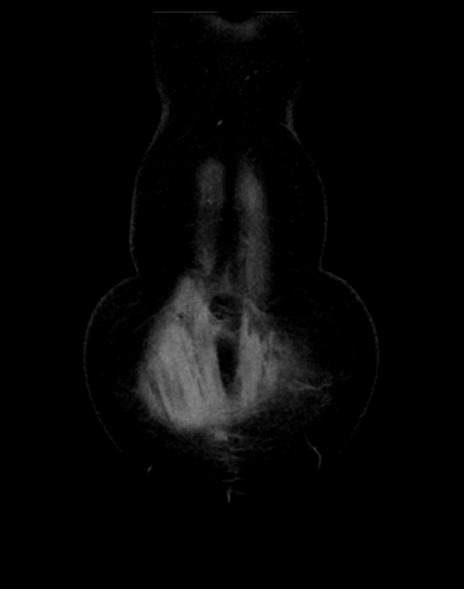

症例13 CT(冠状断像)1日半後